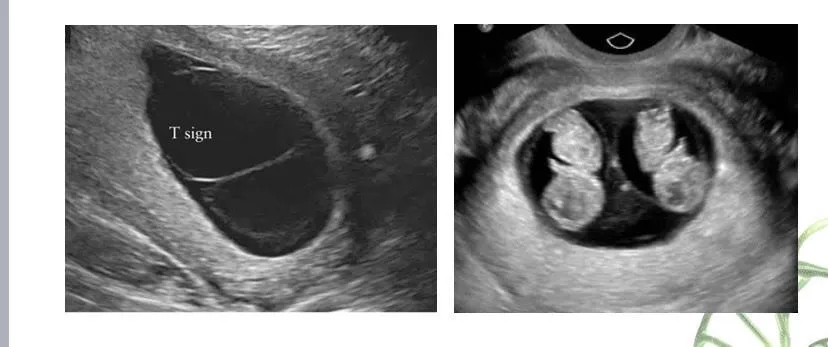

Hình ảnh trường hợp thai nhi bất thường. Ảnh: BV

Theo đó, trường hợp hiếm gặp kể trên là thai phụ 23 tuổi quê ở Nam Định, mang thai tự nhiên lần đầu. Kết quả siêu âm từ tuần thai thứ 8 cho thấy hình ảnh song thai chung một bánh rau, hai buồng ối.

Sau đó, thai phụ đến Bệnh viện Phụ sản Hà Nội thăm khám ở tuần thai 16 vì có một thai phù. Sau khi hội chẩn, siêu âm và chọc ối phát hiện thai A phù thai, giới tính nữ, kiểu gene nữ Turner (45,X);  thai B bình thường về mặt hình thái và giới tính trên siêu âm là nam, kiểu gene nam (46,XY).